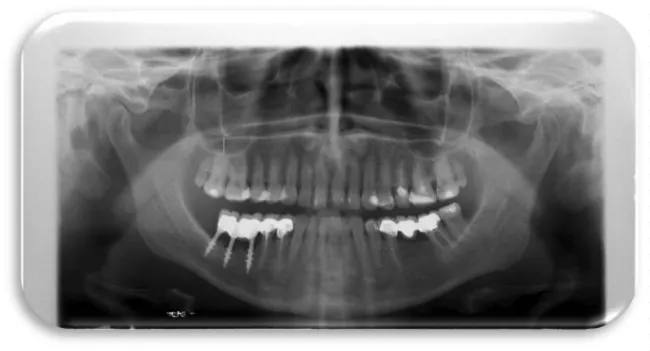

Woman at aged 37 year age, in good health condition and without any systemic diseases, allergic to penicillin came for prosthetic rehabilitation. She was without second premolar and first molar in the lower right quadrant. The patient was provided with dental implants at 45 and 46 (Figures 17-19). After a month on a 45-implant, retrograde peri-implantitis appeared. In chronological order, X-ray images are shown on figures from 17 to 20.

Different treatment strategies were performed in order to remove peri-implantitis. Provided treatment include: debridement of bone tissue, use of bone grafts from known biocompatible grafting materials, i.e. BioOS, disinfection of the surface of the dental implant. After 12 months, another radiography record was made, where ceramic crowns over the implants were seen and there was no longer peri-implantitis (Figure 20) [19,20].